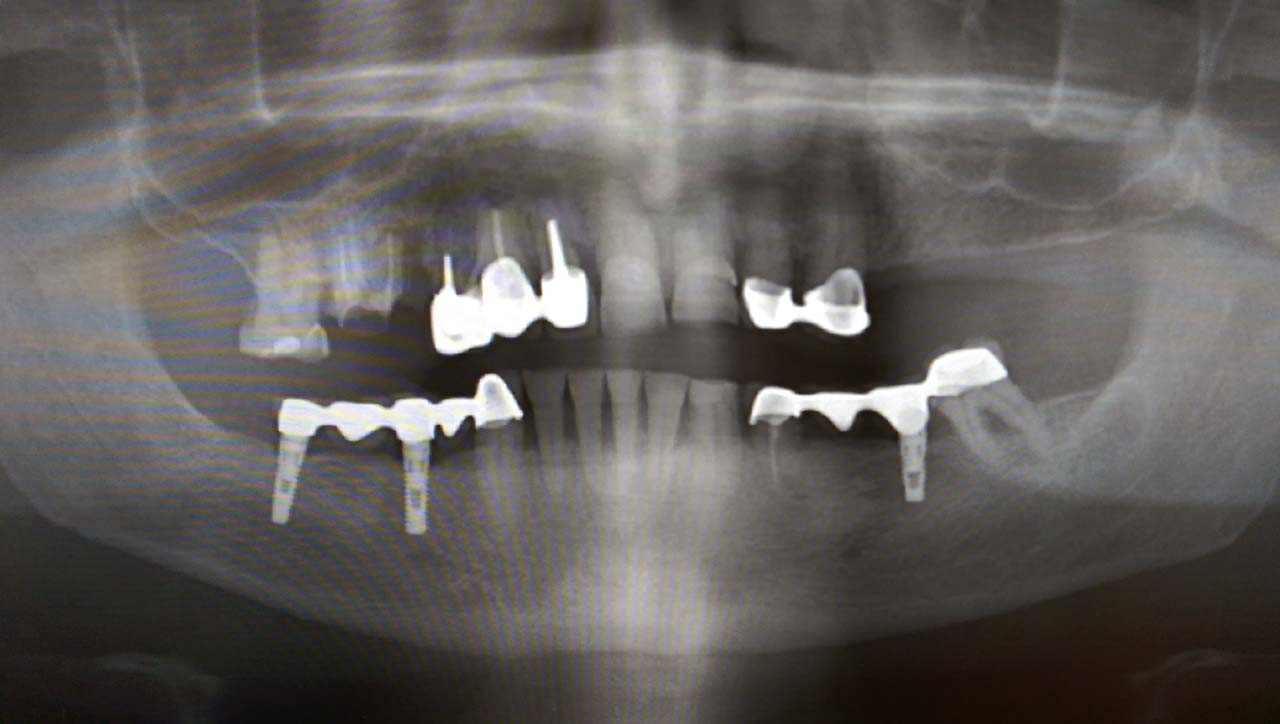

Teljes szájüregi rehabilitáció két lépésben

Ismét egy teljes szájüregi rehabilitáció két lépésben. Először az alsó fogak lettek kihúzva és azonnal implantálva, híddal ellátva, majd később a felső. IHDE svájci azonnal terhelhető implantátumok és cirkónium hidak. Dr. Kelemen Péter és a Symbion Fogtechnika közös munkája.